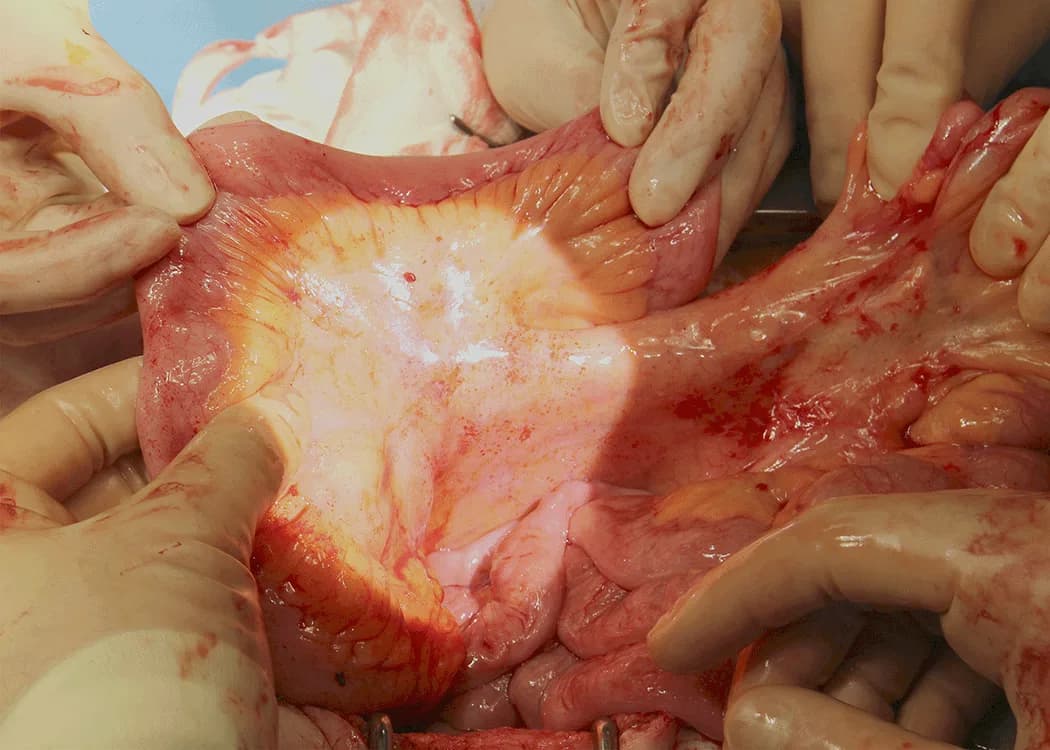

Following embryological analysis, the research expanded into cadaveric dissection, allowing direct anatomical validation of developmental concepts. Cadaver studies provided high resolution insight into structural continuity, fascial planes, and anatomical relationships not fully appreciable through imaging alone.

This phase required careful documentation and comparison across specimens, enabling the research team to test hypotheses derived from embryology against consistent physical findings. Digital capture and organisation of anatomical material played an important role in maintaining longitudinal continuity across years of study.

As the research progressed, intraoperative video recordings became a critical source of real world anatomical evidence. Live surgery provided dynamic, functional confirmation of anatomical principles previously observed in cadavers, allowing structures to be examined in situ under physiological conditions.

These recordings required careful handling, editing, and categorisation to support both research and education. Video material was reviewed frame by frame where necessary, enabling detailed analysis of anatomical planes, vascular relationships, and surgical access routes. This step bridged classical anatomy with modern surgical practice.